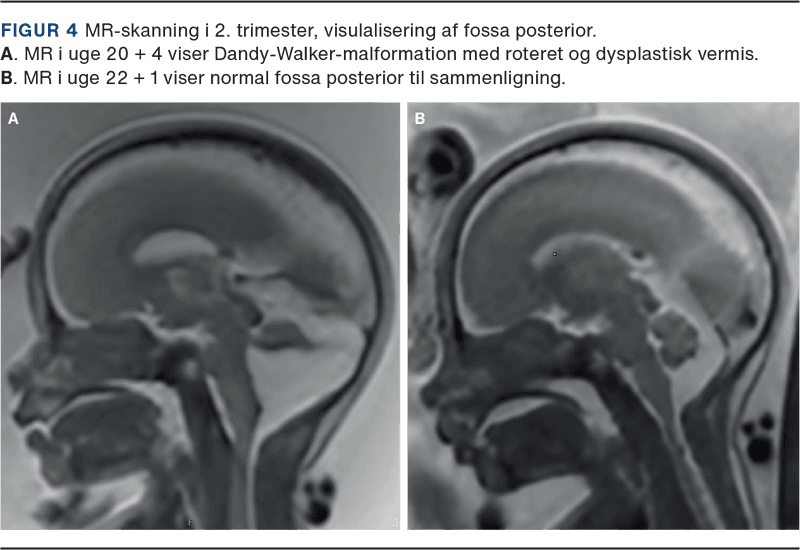

Føtal MR-skanning er en vigtig supplerende undersøgelse til føtalmedicinsk specialist neurosonografi. Formålet er at be- eller afkræfte UL-fund og undersøge for andre/associerede CNS-misdannelser, som kan være væsentlige for en samlet vurdering af prognosen (Figur 4) [15].

MR-skanning har nogle fordele og komplimenterer derfor føtal UL-skanning. MR-skanning er uafhængig af fosterlejring, højt BMI hos den gravide og oligohydramnios. Der kan ved MR-skanning visualiseres flere detaljer ved mistanke om fossa posterior anomalier, ligesom blødninger, vaskulære forandringer, migrationsdefekter og andre malformationer af den kortikale udvikling fremstilles bedre ved MR-skanning. Derimod har UL-skanning en højere spatial opløsning end MR-skanning og kan bedre visualisere f.eks. cystevægge og flow i kar med Doppler. MR-skanning kræver længere undersøgelsestid, hvilket kan være problematisk ved ubehag hos den gravide eller mange fosterbevægelser.

I Danmark foretages ca. 150 MR-fosterskanninger om året ligeligt fordelt mellem København og Aarhus. De fleste MR-skanninger foretages som opfølgning på UL-skanning i 2. trimester. Hyppige indikationer er f.eks. abnorm hjernebiometri, ventrikulomegali, tegn på fokal patologi som iskæmi eller blødning, fossa posterior malformation, midtlinjeanomalier som corpus callosum agenesi og i visse tilfælde ved infektionssygdomme, som kan medføre fosterhjerneskade. Ved mistanke om defekter i spinalkanalen kan nærmere detaljer ved et evt myelomeningocele påvises.